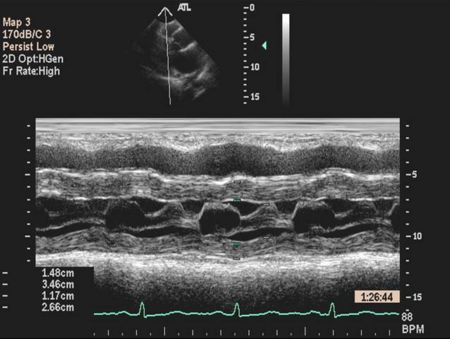

Mitral Valve M-mode Analysis

- Anterior leaflet with E/A appearance of diastology

- Decreased EF slope in MS

- Scalloping of leaflet tip in end systole in prolapse

M Mode in Mitral Stenosis

- Leaflet tips bright (calcified) and thickened

- E/F slope decreased